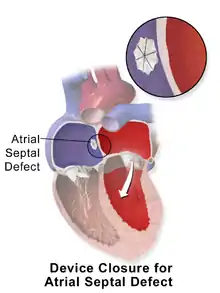

| Illustration of an atrial septal defect. | |

Catheter procedure

Percutaneous device closure involves the passage of a catheter into the heart through the femoral vein guided by fluoroscopy and echocardiography.[13] An example of a percutaneous device is a device which has discs that can expand to a variety of diameters at the end of the catheter. The catheter is placed in the right femoral vein and guided into the right atrium. The catheter is guided through the atrial septal wall and one disc (left atrial) is opened and pulled into place. Once this occurs, the other disc (right atrial) is opened in place and the device is inserted into the septal wall. This type of PFO closure is more effective than drug or other medical therapies for decreasing the risk of future thromboembolism.[13][47][48] The most common adverse effect of PFO device closure is new-onset atrial fibrillation.[49] Other complications, all rare, include device migration, erosion and embolization and device thrombosis or formation of an inflammatory mass with risk for recurrent ischemic stroke.[50][51]

Percutaneous closure of an ASD is currently only indicated for the closure of secundum ASDs with a sufficient rim of tissue around the septal defect so that the closure device does not impinge upon the superior vena cava, inferior vena cava, or the tricuspid or mitral valves. The Amplatzer Septal Occluder (ASO) is commonly used to close ASDs. The ASO consists of two self-expandable round discs connected to each other with a 4-mm waist, made up of 0.004– to 0.005-inch Nitinol wire mesh filled with Dacron fabric. Implantation of the device is relatively easy. The prevalence of residual defect is low. The disadvantages are a thick profile of the device and concern related to a large amount of nitinol (a nickel-titanium compound) in the device and consequent potential for nickel toxicity.